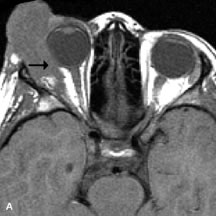

MRI is an excellent modality for demonstrating enlargement of the cavernous sinus and dilation of the superior ophthalmic vein in patients with high-flow carotid-cavernous fistulas (Fig. 14).37MRA may be helpful in the evaluation of the venous outflow pattern. The rapidly flowing blood in these vascular structures carries the excited protons out of the section before they can be imaged, resulting in their dark appearance.5 In low-flow dural arteriovenous malformations, MRA may help define the arterial feeding vessels.45

Fig. 14. Patient with Ehlers-Danlos syndrome who presented with abrupt onset of severe proptosis. A-C. Postcontrast fat-suppressed T1-weighted MR scans demonstrate marked proptosis and engorgement of the extraocular muscles and superior ophthalmic vein (arrows). D. T2-weighted scan through the cavernous sinus demonstrates enlargement and arterialized flow void within the right cavernous sinus (open arrow).